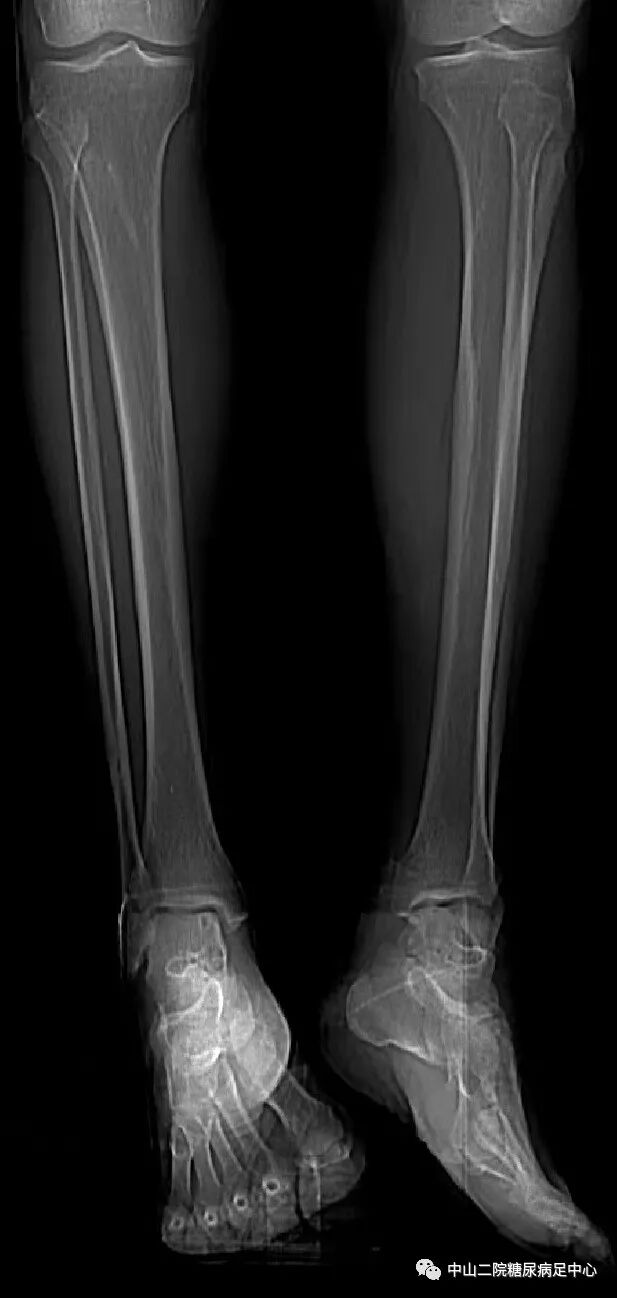

入院前急诊检查(9月18日):

腿部CT:

伤口负压治疗怎么收费54天,治愈一例小腿胫前溃疡的糖尿病病人!_https://www.jmylbn.com_新闻资讯_第3张

左侧胫骨中段前内侧软组织肿胀,考虑感染性病变,需注意化脓性感染。